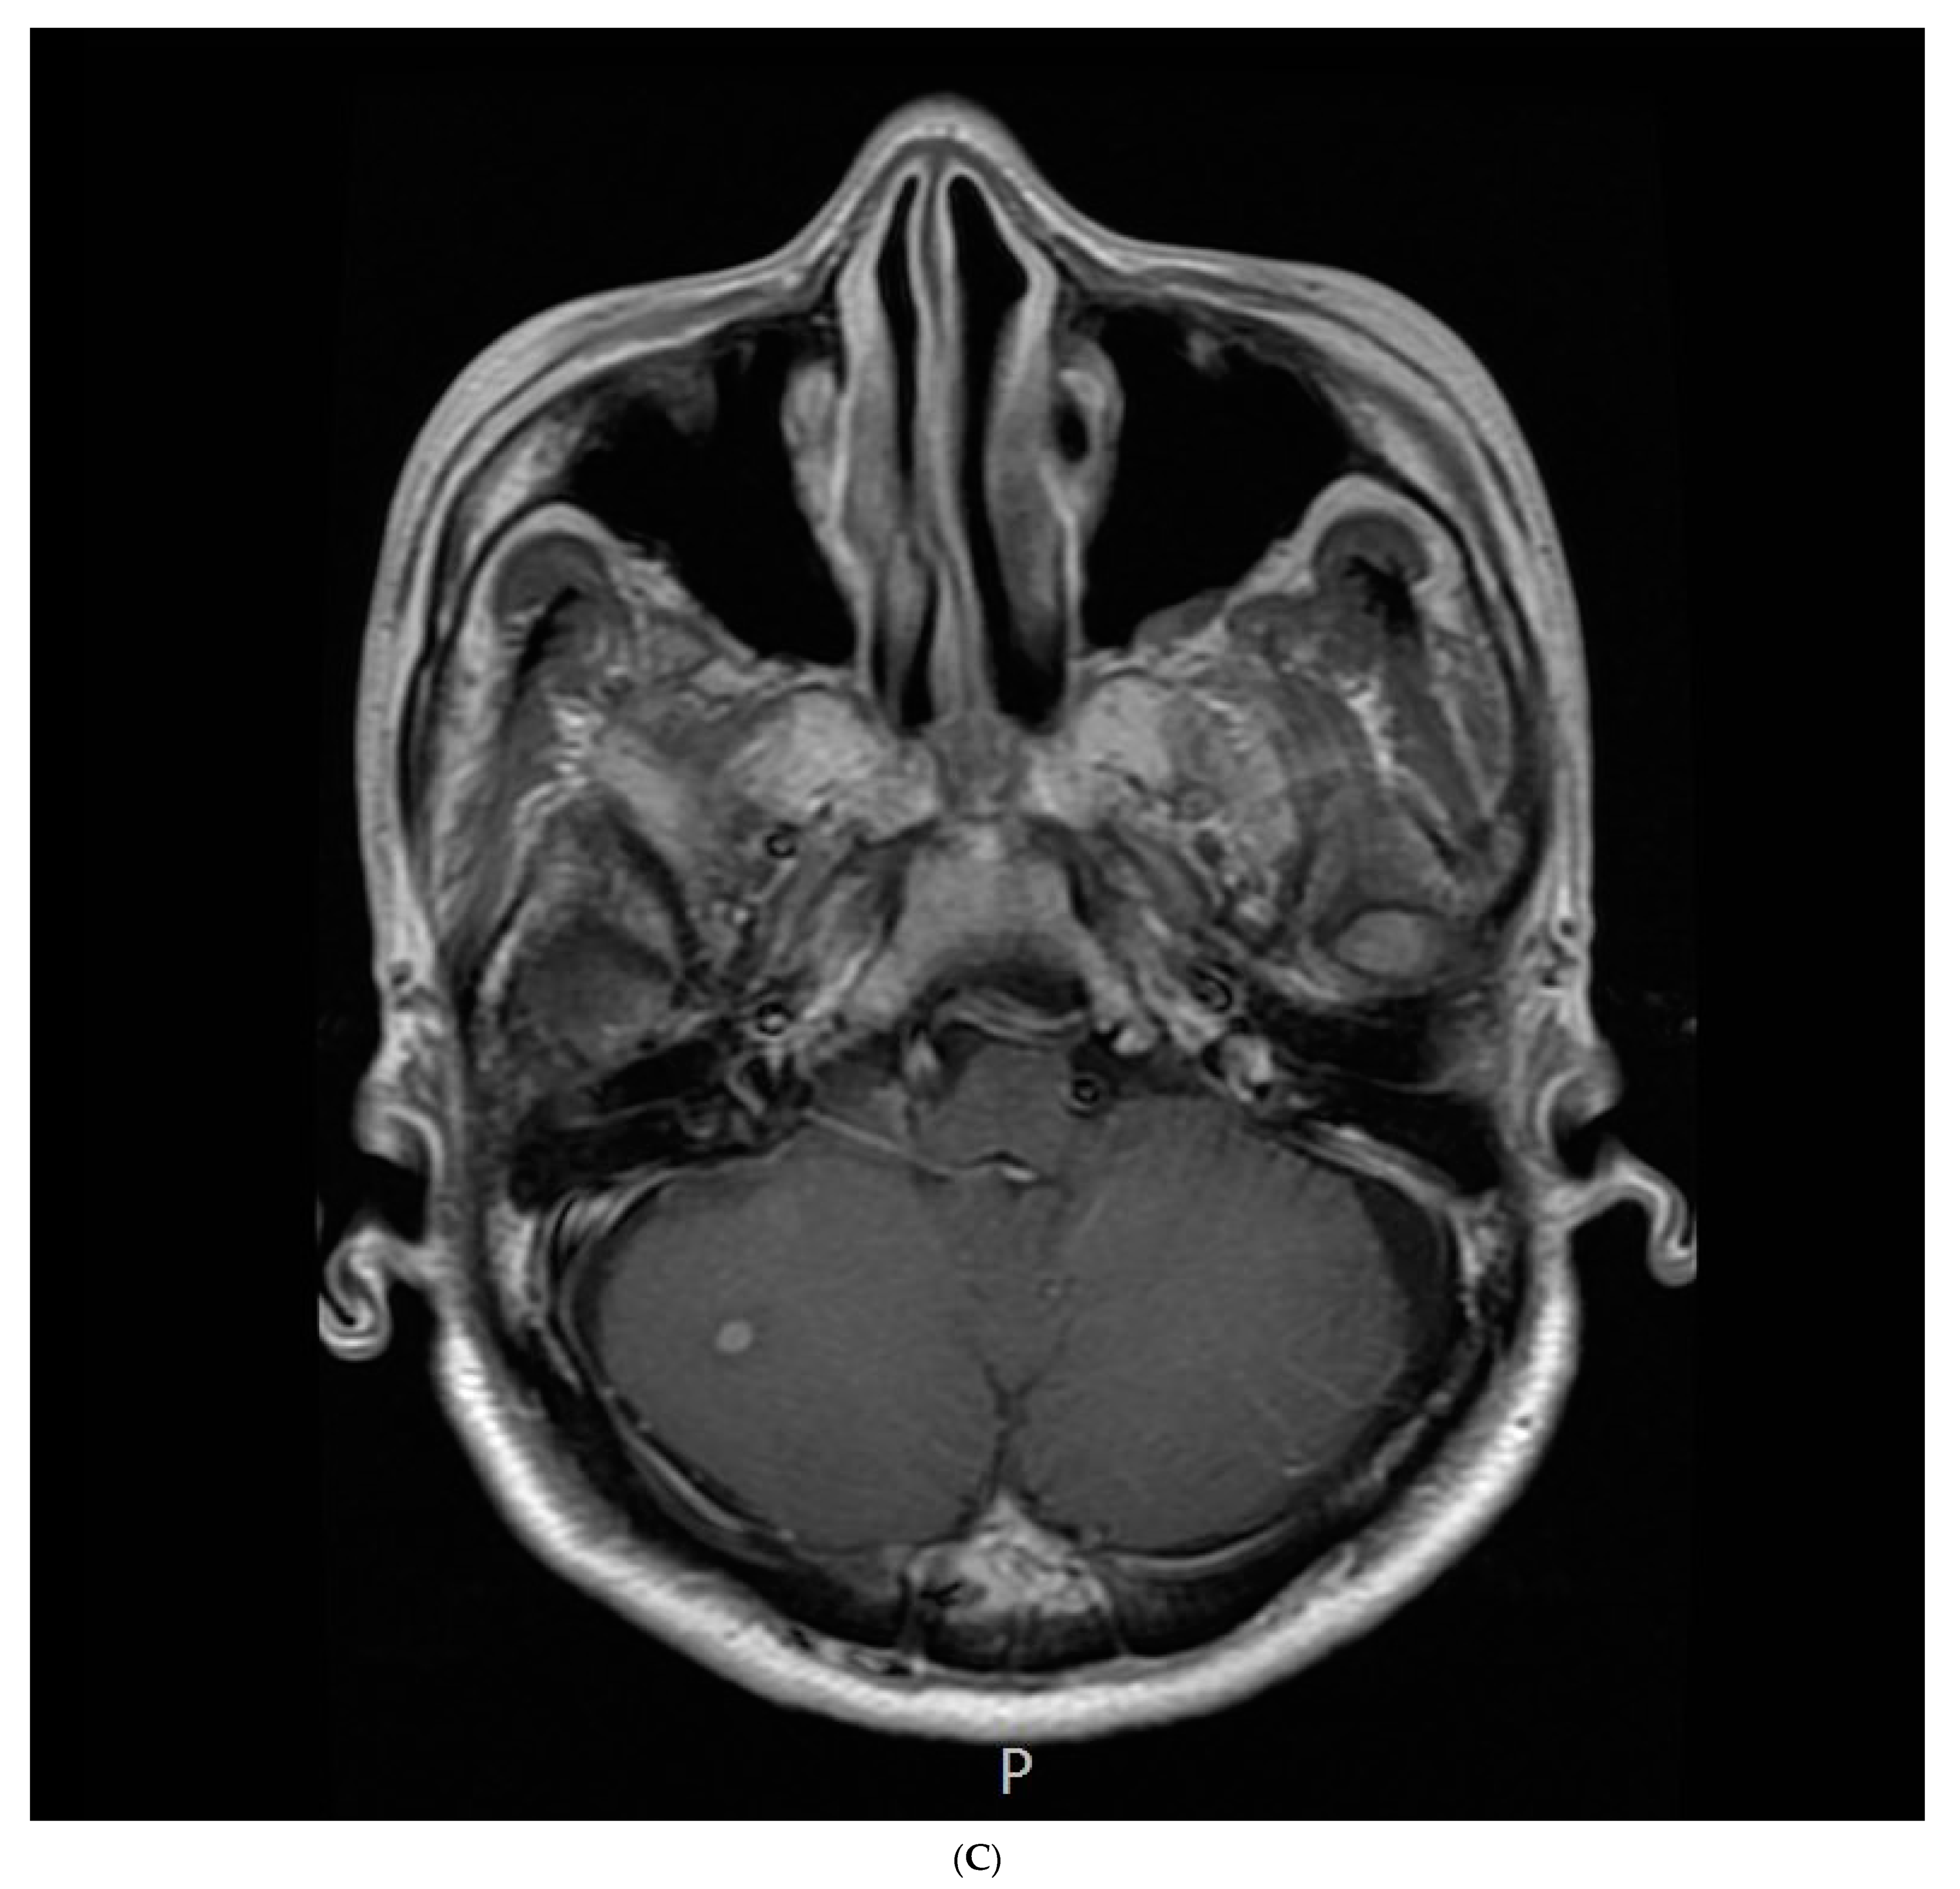

2. Case Report